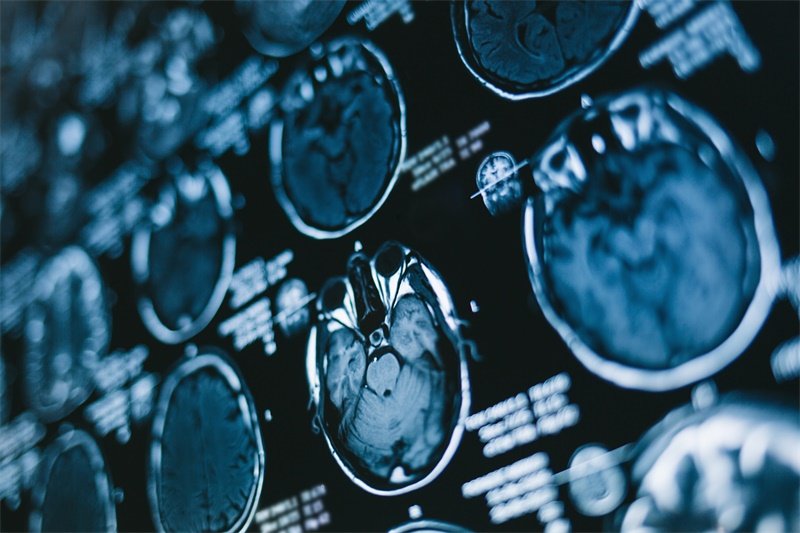

影像学检查不可少:增强MRI能清晰显示占位与神经根的关系,鉴别血供情况(良性多均匀强化,恶性多混杂强化);CT可评估骨质破坏细节,如转移性肿瘤的溶骨性改变或椎间盘钙化的高密度影。这两项检查相互补充,是判断病变位置、大小及侵袭性的关键。